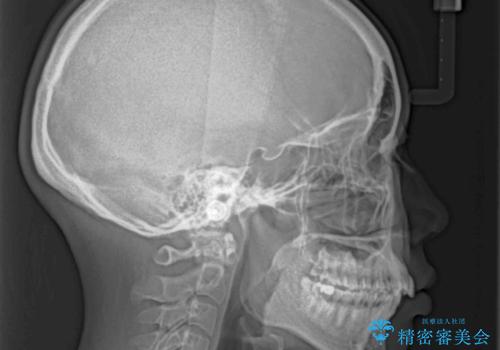

前歯のデコボコを抜歯矯正で改善 メタル装置で費用を抑える

- 前歯のデコボコと口元の突出感を気にして来院された患者様です。

非抜歯矯正ではデコボコを解消することでより口元が突出してしまうため、上下左右の小臼歯4本の抜歯を行い、ワイヤー装置による矯正治療を行うこととしました。

もう少し口元の突出感を改善したかったのですが、舌の突出癖が影響し下顎前歯が唇側に押させる仕上がりとなりました。